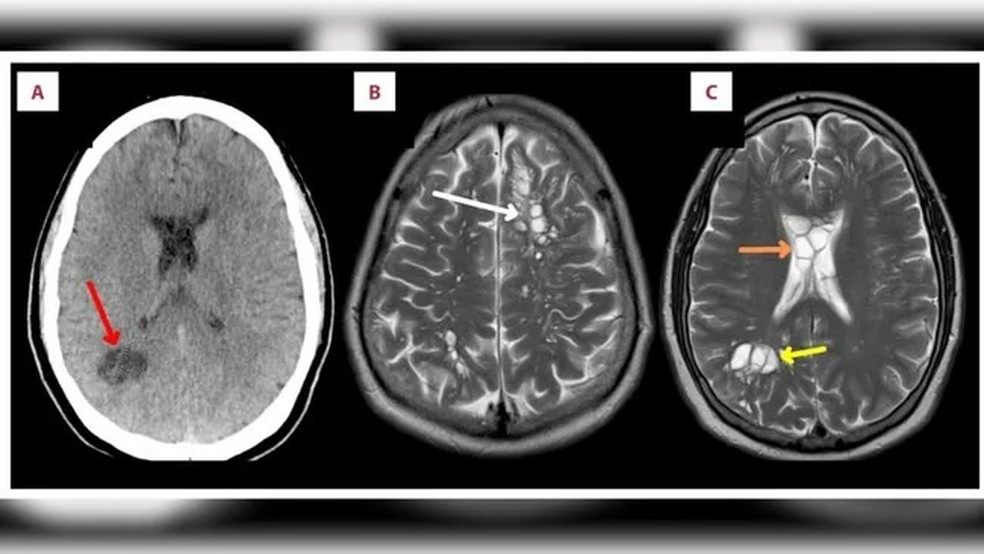

Imagens do cérebro após a contaminação com a tênia — Foto: Reprodução/American Journal of Case Reports

Quando chega ao cérebro (neurocisticercose),o paciente pode ter dores de cabeça frequentes,convulsões e confusão mental,sendo uma das principais causas de convulsões em adultos na maioria dos países de baixa renda,de acordo com os Centros de Controle e Prevenção de Doenças (CDC),dos Estados Unidos.

Já a cisticercose ocular pode desenvolver visão embaçada,inchaço,deslocamento da retina e até mesmo levar à cegueira.

Os sintomas podem ocorrer meses a anos após a infecção,geralmente quando os cistos começam a morrer. Quando os cistos morrem,o cérebro ou outro tecido ao redor do cisto pode inchar. A pressão do inchaço é o que geralmente causa os sintomas da infecção. Às vezes,os sintomas são causados pela pressão do cisto em um pequeno espaço,segundo o CDC.